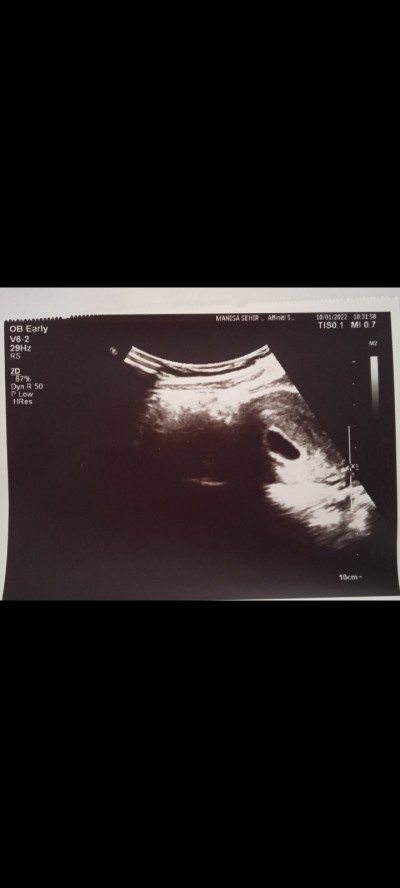

Merhaba arkadaşlar iyi akşamlar rica etsem ultrason resmine bakar mısınız tecrübeli olanlar anlaya bilir mi yazılar falan kese, doktor ilgisiz di biraz bir dahaki randevum iki hafta sonra o yüzden soruyorum teşekkür ederim

Gebelik haftası 5

Kese oluşmuş ama bebeğin oluşumu dha yok 4 hatfalik mı

Tatlim kese gorunmus bebek gorunmuo cok kucuk oldgu icin 2 hfta sonra tahmini gorunr belki kalp atisinda duyarsn.bazen bebek gorunmeyince doktr ugrasmio benmkide oyleydi keseyi gordu 2 hfta snra gel demisti.bi sorun yok yani icin raht olsn

Kese oluşmuş 2 hafta sonra gittiginizde hem bebeği görür hem kalp atışını alirsniz Allah tamamına erdirsin inşallah